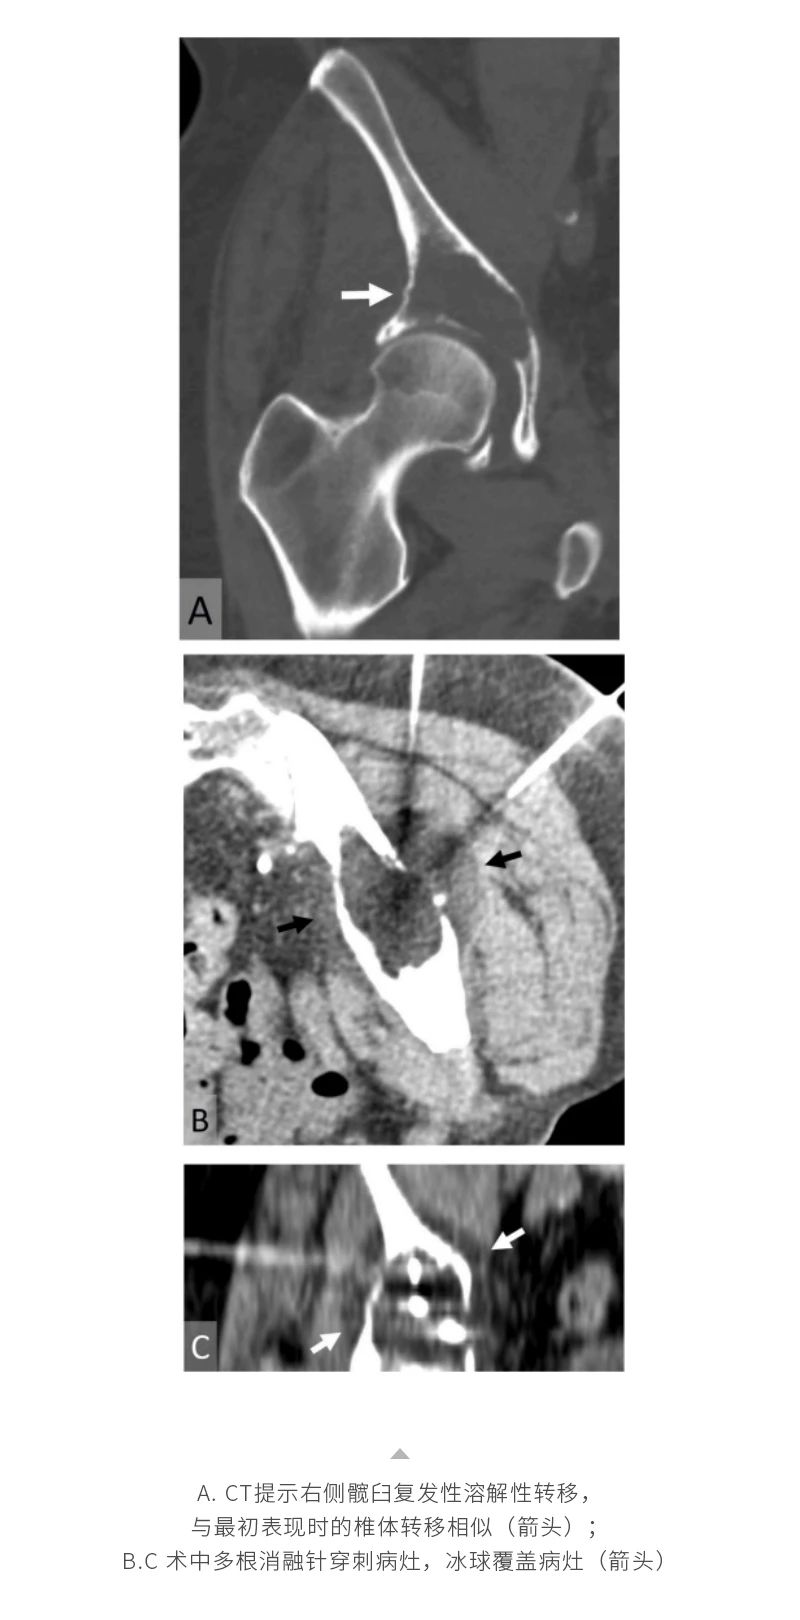

冷凍消融骨腫瘤——【海杰亞科研資訊】第285期

發(fā)布時(shí)間:2024-10-18 | 作者:海杰亞 | 瀏覽次數(shù):1414